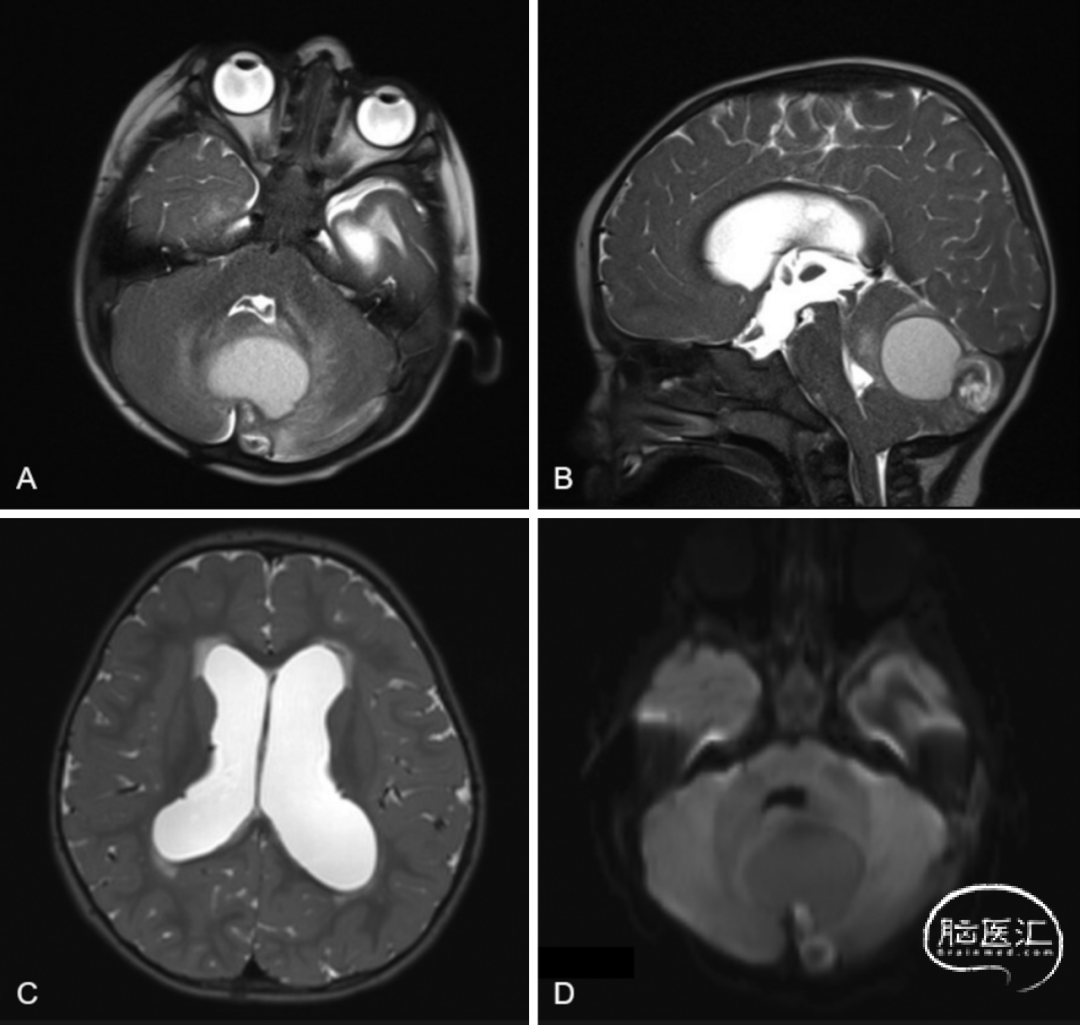

■ 脑部MRI显示后颅窝占位性病变(2.6×3×2.7cm),压迫小脑蚓部,伴幕上脑室扩大(图2)。因病变体积大、有占位效应,伴梗阻性脑积水及神经功能恶化,决定再次手术。

图2. 随访MRI检查显示小脑中线病变,伴继发性幕上脑室扩大,病变后部致密部分存在弥散受限,符合皮样囊肿表现。